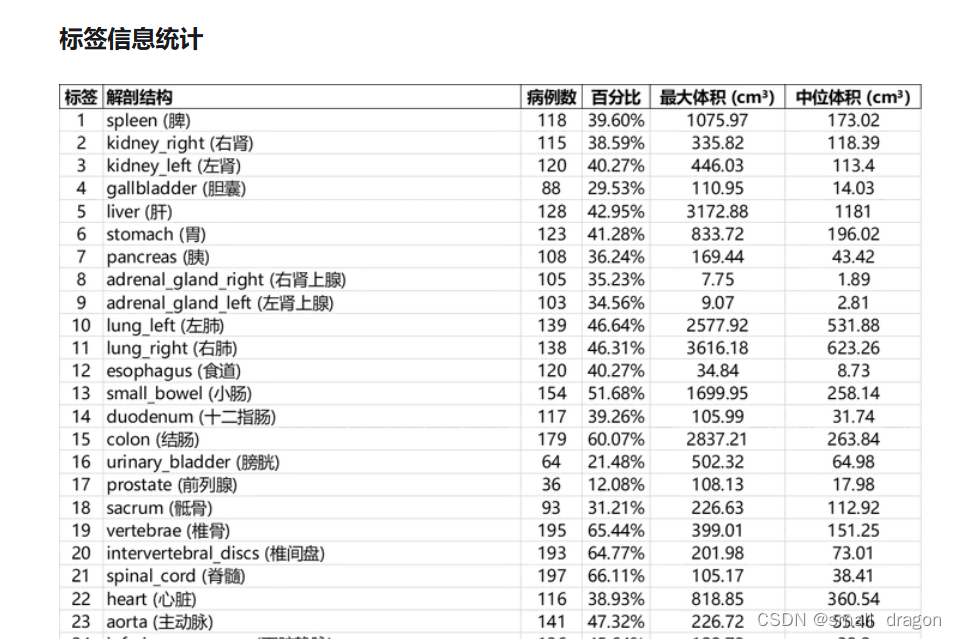

标签信息统计